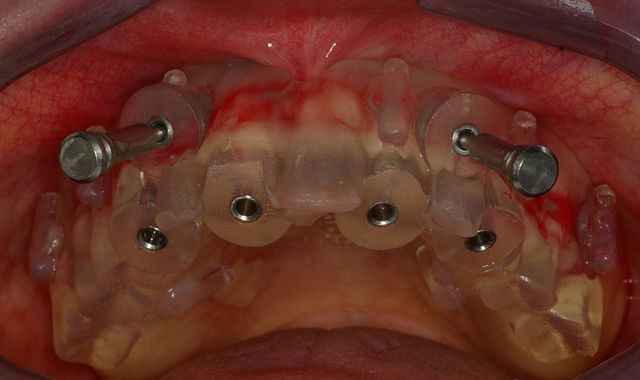

Fig. 3 Fig. 4

Within a couple weeks, the CT-based pilot surgical guide (3DDX) was received in our office and tried in for verification of proper fit. The area was anesthetized and the sites for the implants was initiated with a 1.95 mm pilot drill through the surgical guide (Fig. 3) utilizing the AEU-7000 surgical motor (Aseptico) at a speed of 1200 rpm with copious amounts of irrigation. Paralleling pins (Fig. 4) were then placed in the site of the osteotomies to confirm the accuracy of the surgical guide.

Fig. 5 Fig. 6

Using a rotary tissue punch (OCO Biomedical), an outline cut was created over the initial osteotomies and the tissue plugs were removed with a curette (Goldendent). Once the osteotomy sites were completed with sequential osteotomy formers, the dental implants were placed (Fig. 5) with the surgical handpiece at a speed of 25. The ratchet wrench was then connected in order to torque the dental implants to final depths reaching a torque level of about 25-30 Ncm.